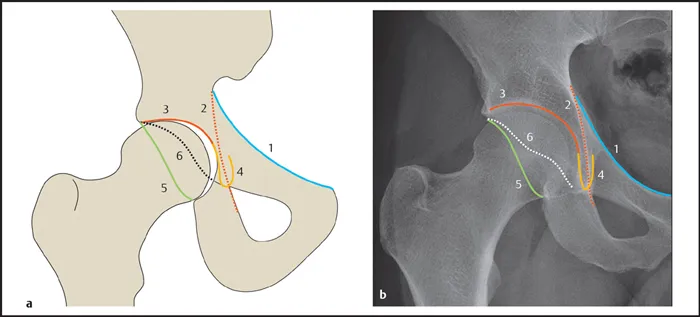

- Key Lines for Hip Assessment (AP View):

- Hilgenreiner's Line: Horizontal line through bilateral triradiate cartilages.

- Perkin's Line: Vertical line perpendicular to Hilgenreiner's at the lateral acetabular margin.

- Shenton's Line: A continuous, smooth arc from the medial femoral neck to the inferior pubic ramus.

- Klein's Line: Drawn along the superior border of the femoral neck; femoral head should intersect it. Crucial for SCFE diagnosis.

- Acetabular Angle: Formed by Hilgenreiner's line and acetabular roof. Normal: <30° at birth.

⭐ A disrupted Shenton's line is a key indicator of a femoral neck fracture or developmental dysplasia of the hip (DDH).